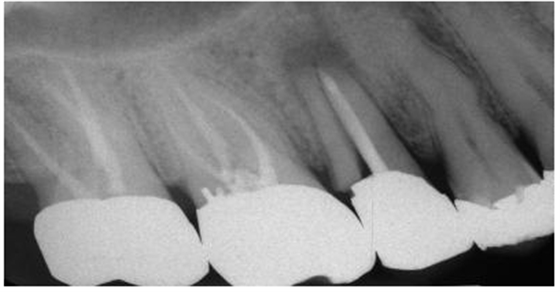

圖1:上頜第二前磨牙根折的根尖片,經(jīng)由預(yù)成金屬樁修復(fù)